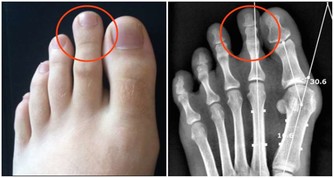

7、在抬腳時,脊椎保持水準,全身肌肉富有彈性,氣血順暢,各關節自會增生骨髓,脊椎兩旁神經恢復平常傳導作用。